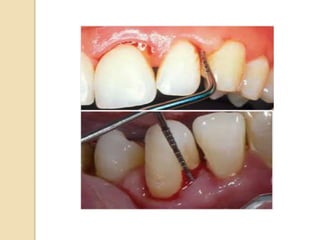

 It is used for evaluation of gingival inflammation.

 For record the index retract the cheek & place the

periodontal probe 1mm into the sulcus or pocket at the

distal aspect of the most posterior tooth in the quadrant on

the buccal surface.

 Carry the probe lightly across the length of the sulcus to the

mesial interproximal area on the facial aspect.

 Wait for the 30 sec. & record the presence of bleeding on

the distal, facial & mesial surface.

 Repeat the same for palatal/lingual surface.

 Percentage of the number of bleeding surfaces is calculated

by dividing the number of the surfaces that bled by the total

no. of tooth surface(4 per tooth) & by multiplying by 100.

 Goal of 10% or fewer bleeding points is good, but 0 is ideal.